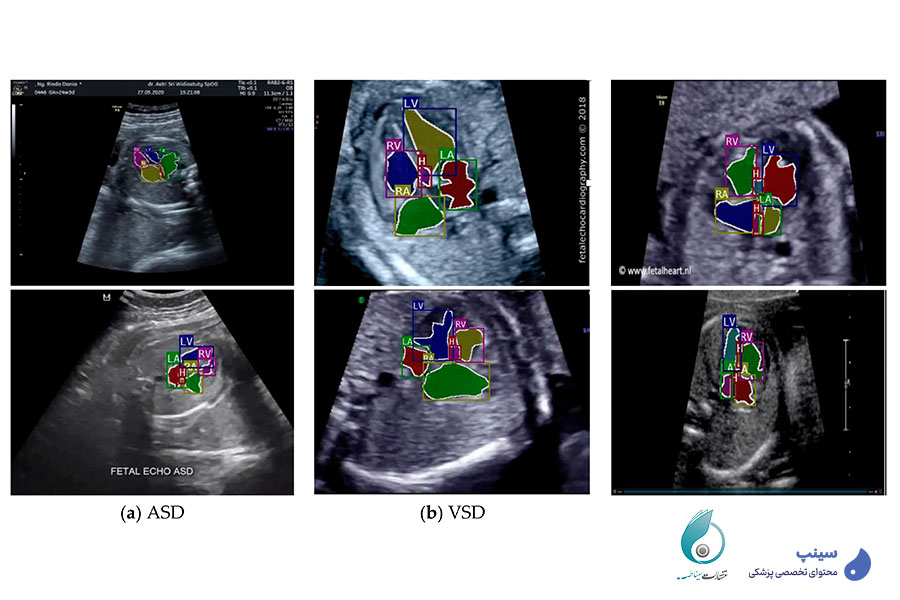

بررسی بیماری‌های مادرزادی قلبی: بیماری‌های مادرزادی قلبی شامل ناهنجاری‌هایی مانند نقص دیواره بین بطنی (VSD) و نقص دیواره بین دهلیزی (ASD) هستند که بر نحوه گردش خون داخل قلب تأثیر می‌گذارند. تترالوژی فالوت یکی از شایع‌ترین نواقص مادرزادی است که موجب انسداد جریان خون ریوی می‌شود. در این بخش، پزشکان با این ناهنجاری‌ها و نحوه تشخیص آن‌ها از طریق اکوکاردیوگرافی آشنا خواهند شد.

تشخیص موارد طبیعی و غیرطبیعی در تصاویر اکوکاردیوگرافی جنین: برای تفسیر صحیح تصاویر اکوکاردیوگرافی، پزشک باید تفاوت بین ساختارهای طبیعی و ناهنجاری‌های قلبی را تشخیص دهد. برخی واریانت‌های طبیعی ممکن است شبیه بیماری‌های مادرزادی به نظر برسند، اما با بررسی دقیق الگوهای جریان خون و ساختارهای آناتومیکی، می‌توان آن‌ها را از موارد پاتولوژیک افتراق داد.